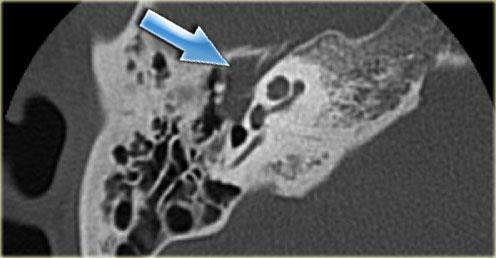

Bên trái là hình ảnh cắt ngang và cắt vành của một bệnh nhân nam 50 tuổi.

Phát hiện tình cờ túi thừa hành tĩnh mạch cảnh (mũi tên).